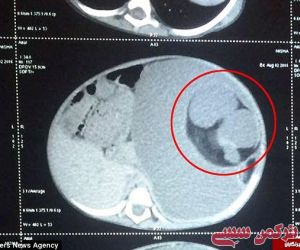

به گزارش خبرنگار ترکمن سسی به نقل از باشگاه خبرنگاران جوان،در کشور هندوستان یک دختر بچه 15 ماهه به نام نیشا به وسیله پزشکان تحت عمل جراحی قرار گرفته و از معده او دو جنین تکامل نیافته به اندازه دو توپ تنیس خارج شده است.

این جنین ها در واقع دو قلوهای همراه نیشا بوده اند که در یک پدیده عجیب که تنها 200 مورد از آن تا به حال در دنیا شناسایی شده است به جای رشد در رحم مادر درون یکی از جنین ها بزرگ می شوند.به دلیل نقص ژنتیکی شدید تکامل آنها تا 9 ماهگی کامل نشده و تنها پس از تولد نیشا با استفاده از بند ناف از او تغذیه کرده و بافت سلولی آنها افزایش یافته است.

این بیماری به نام foetus in fetu بسیار نادر است و معمولاً در بدن مادری که بارداری چند قلویی را پشت سر گذاشته مشاهده می شود، در این اختلال اجزایی چون پوست، گوشت، مو، استخوان و کلسیم به صورت ناقص در بدن شکل می گیرند.

پزشکان در ابتدا تصور می کردند که یک توده سرطانی در بدن نیشا در حال رشد است اما پس از اسکن از شکم او دریافتند که دو قلو های انگلی در بدن او تشکیل و در حال استفاده ازخون و منابع غذایی بدن او هستند.

پزشکان در یک عمل جراحی 2 ساعته موفق به خارج کردن دوقلوهای انگلی شده اند که به اعضایی چون پانکراس، کلیه و معده کودک وصل شده بودند.